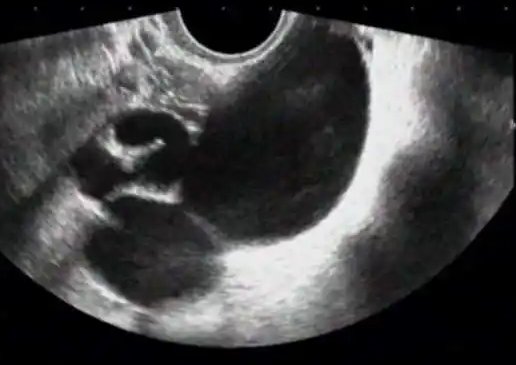

2024-03-27做試管的過程中少不了陰超檢查,陰超可以檢查很多問題,其中包括卵泡發(fā)育、子宮內(nèi)膜厚度等問題都是可以快速了解的。對于做試管的女性來說,陰超肯定是要做的,至于幾次要看...